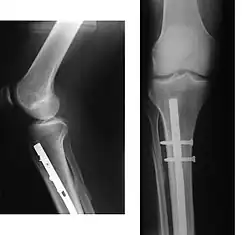

An intramedullary rod, also known as an intramedullary nail (IM nail) or inter-locking nail or Küntscher nail (without proximal or distal fixation), is a metal rod forced into the medullary cavity of a bone. IM nails have long been used to treat fractures of long bones of the body. Gerhard Küntscher is credited with the first use of this device in 1939,[1][2] during World War II, for soldiers with fractures of the femur. Prior to that, treatment of such fractures was limited to traction or plaster, both of which required long periods of inactivity. IM nails resulted in earlier return to activity for the soldiers, sometimes even within a span of a few weeks, since they share the load with the bone, rather than entirely supporting the bone.[3]

Although stainless steel was used for older IM nails, titanium has several advantages, including lower mechanical failure rates and improved biocompatibility.[6] The discovery of the outstanding biocompatibility of Tantalum in the late 1930s by Gerald Burke allowed for significant advances in orthopaedics due to the long-term strength and stability of tantalum implants and fasteners. [7] A more significant problem with earlier designs was their failure to prevent collapse or rotation in inherently unstable fractures. This was addressed by the introduction of the concept of 'locking' the nails, where bolts on each end of the nail fix it to the bony cortex, preventing rotation among the fragments. This led to the emergence of locked IM nailing, which is the standard today.[3]Truly permanent surgical fittings could now be predicted from the relative strength of the fasteners combined with the biocompatibilty of the metals.